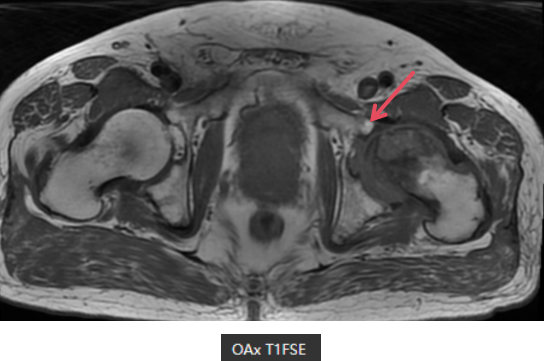

MR表现

左侧股骨头变扁,局部塌陷,骨质内见线状T1WI低信号,髋臼及股骨近端骨松质见片状T1WI低、T2WI压脂高信号,DWI高信号,周围滑膜增厚,邻近软组织肿胀,PD压脂信号增高,关节腔少量积液。